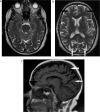

Balint's syndrome is a rare disorder characterized by a triad of simultanagnosia, optic apraxia, and ocular apraxia. The syndrome manifests when there is an injury to the posterior parietal and occipital lobes and is often bilateral. Several causes of this syndrome were published in the literature, such as trauma, infarctions, infections, tumors, and pre-eclampsia. It can also be the presenting feature of several neurodegenerative disorders, such as atypical Alzheimer's disease. We report a case of a 62-year-old lady who presented with simultanagnosia, optic apraxia, and ocular ataxia which are the typical signs and symptoms of this syndrome. Neuropsychological evaluation revealed severe affection of the visual-spatial function with intact memory, language, and cognition. Brain imaging confirmed atrophy and decreased perfusion in the posterior parietal and occipital lobes. No underlying cause could be identified to explain the brain parenchymal atrophy. The follow-up neuropsychological assessment and brain imaging did not show any progression confirming the static course of the disease.